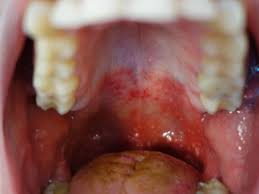

Red Spots On Roof Of Mouth Causes And Other Symptoms

Red Spots On Roof Of Mouth Causes And Other Symptoms from cdn-prod.medicalnewstoday.com